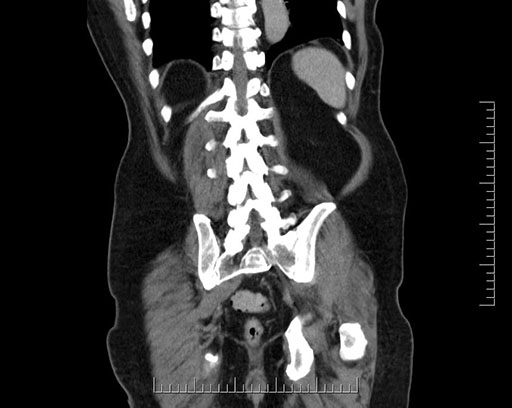

Imaging Analysis

Look through the patient's CT scan to identify any areas of concern for the necessary procedure.

Based on your CT findings, which issue(s) would give reason for "planned slowing down moment(s)" in this case?

Considering a standard Whipple procedure, what step(s) of the operation would you do differently in this case?